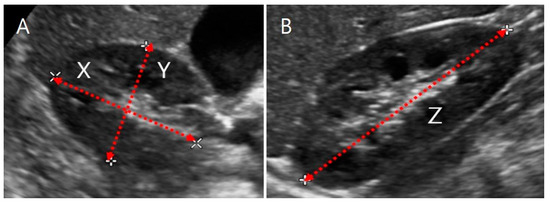

2.3.1. US Images and Ellipsoidal Method